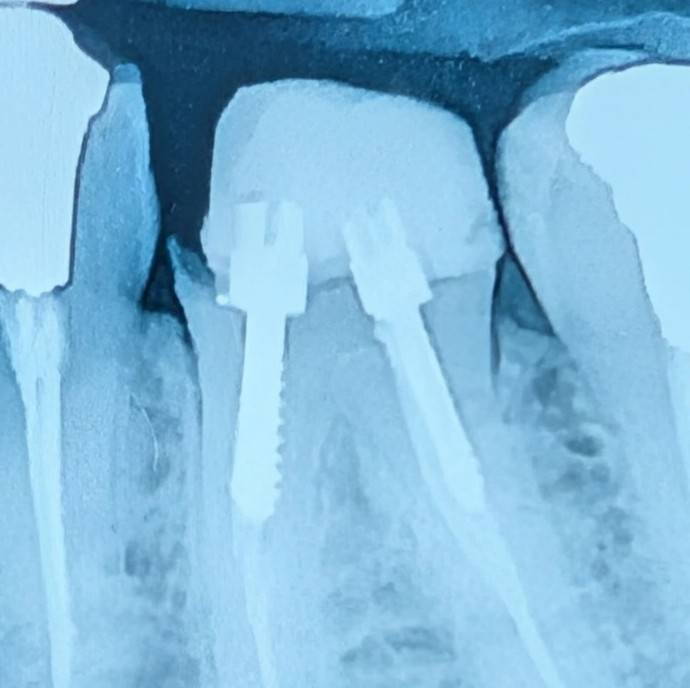

- بیمار با شکایت اصلی در ناحیهای دیگر مراجعه کرده بود. در معاینه، دندان ۶ پایین چپ توجه را جلب کرد. یک ترمیم کامپوزیت بیلدآپ بیکیفیت و بدون باند درست مشاهده میشد که با عود پوسیدگی و لیکیج همراه بود. بخش قابل توجهی از ساختار تاجی از بین رفته بود و عملاً فرولی وجود نداشت.

- با توجه به شرایط باقیماندهٔ دندان، اگر قرار باشد این دندان برای روکش حفظ شود، ابتدا نیاز به درمان مجدد ریشه خواهد داشت. پس از آن، برای ایجاد فرول کافی باید جراحی افزایش طول تاج انجام شود.

- اما در این دندان یک محدودیت مهم وجود دارد: با توجه به موقعیت پوسیدگی و میزان از دست رفتن ساختار و محل استخوان و فورکا، افزایش طول تاج احتمالاً به درگیری فورکیشن نزدیک خواهد شد. در چنین شرایطی حتی اگر درمانها انجام شوند، پیامدهایی مانند گیر غذایی و مشکلات پریودنتال قابل انتظار است.